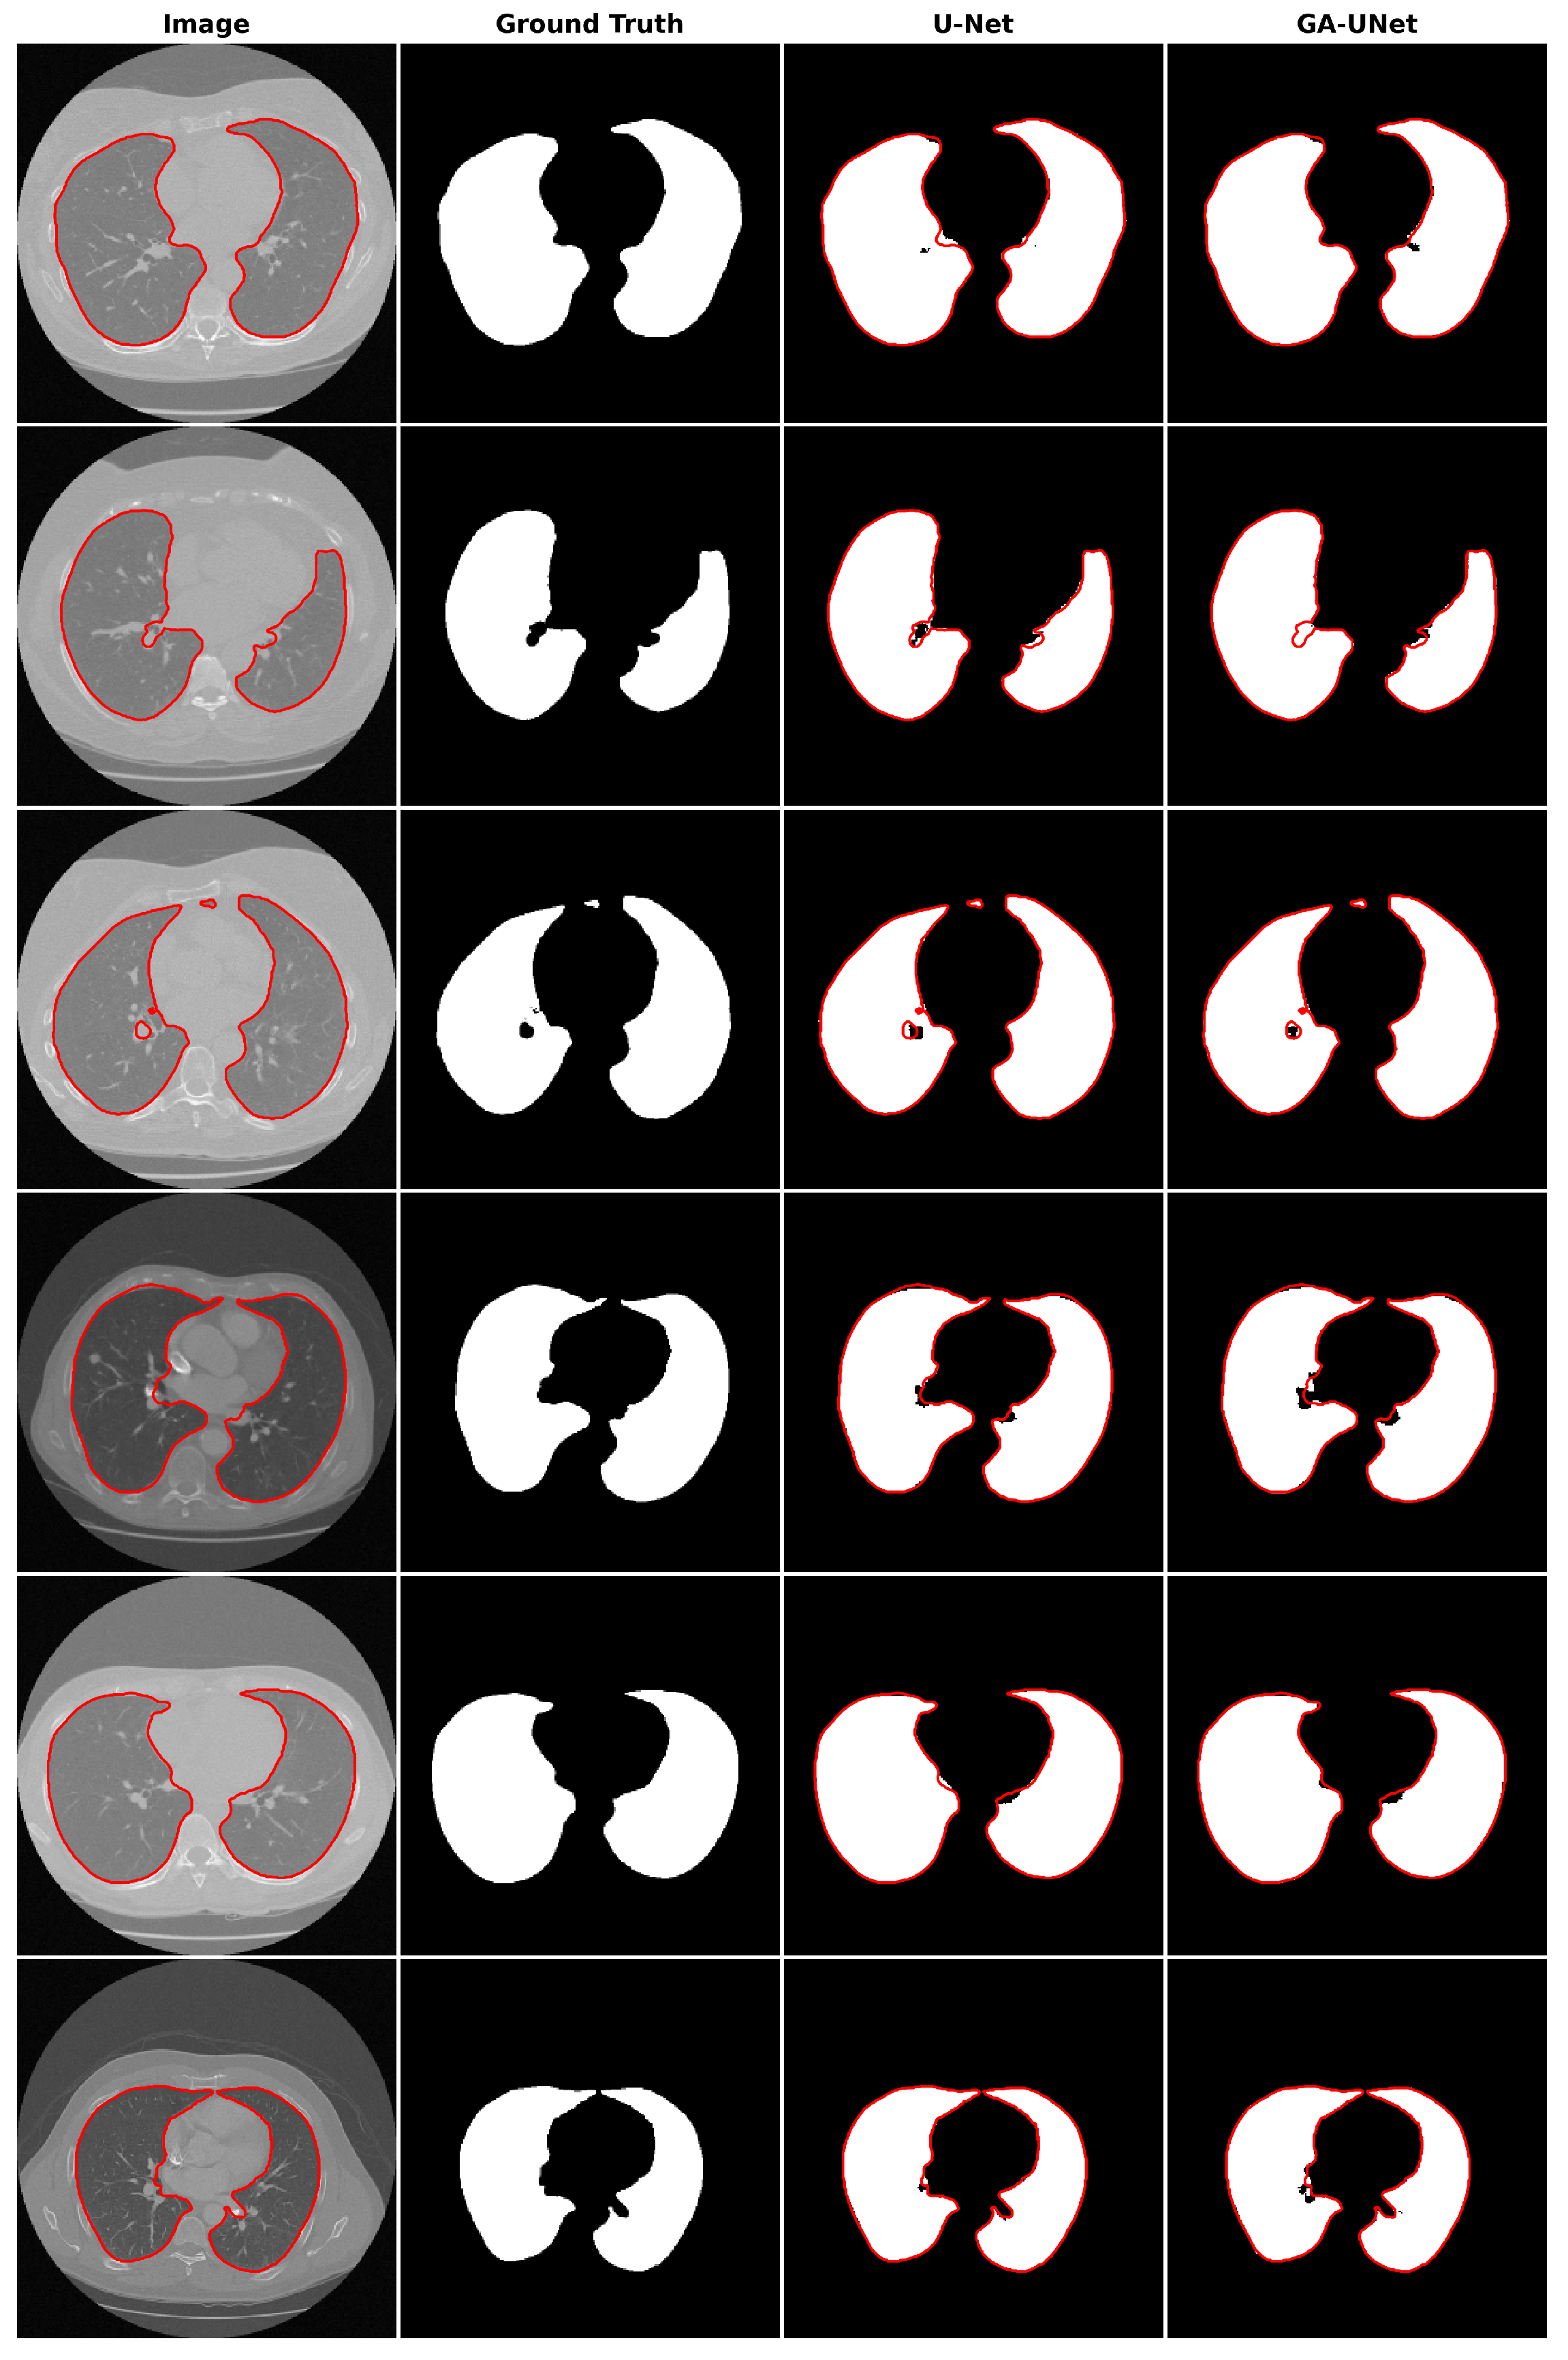

In this experiment, the discovered model was trained for 100 epochs, and its performance was subsequently evaluated against that of the baseline model, U-Net [12]. Figure 7 displays the accuracy and loss plots of the discovered architecture and the original U-Net [12] for the two training and validation phases. The first two plots (a) and (b) in Figure 7 show the accuracy of training and validation data during the training of the models for the lung segmentation dataset; the two graphs show that the discovered model performs well during the training and validation phases compared to the original U-Net [12]. The accuracy graphs of the GA-UNet and U-Net [12] models showed a significant increase during the first 20 epochs and 15 epochs, respectively, after which the rate of improvement slowed down and eventually became nearly constant. Furthermore, the loss for both training and validation data during the training of the models for the lung segmentation dataset are shown in the graphs (c) and (d) in Figure 7. These graphs show that the discovered model has good performance. It can be seen that the loss of the discovered model for both phases, training and validation, significantly decreased during the initial 30 epochs, which is followed by a period of relative stability. Based on the information presented in the four graphs of Figure 7, it can be concluded that the model designed by our proposed method performs well in accurately segmenting the lung from abdominal CT scan images.

Figure 7.

Accuracy and loss plots during training and validation phases of the proposed GA-UNet and the original U-Net [12] for the lung segmentation dataset. (a) Training accuracy plots, (b) Validation accuracy plots, (c) Training loss plots, and (d) Validation loss plots.